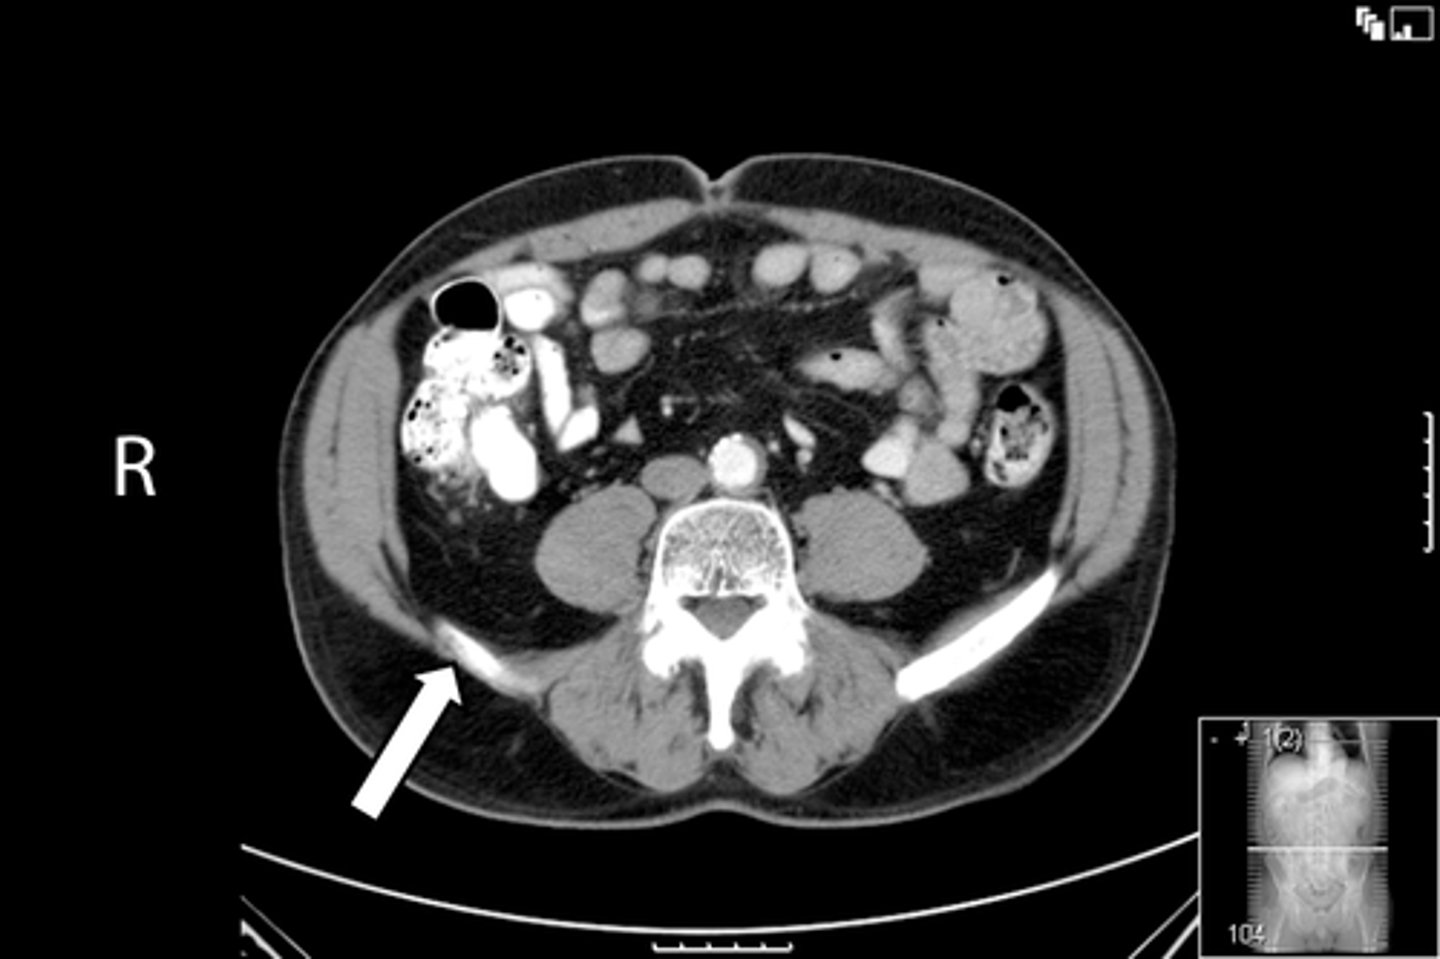

New cards

Axial male pelvis CT

What is the image?

<p>What is the image?</p>

78

Descending colon/sigmoid colon juncture

What is indicated in the image?

<p>What is indicated in the image?</p>

79

L external iliac artery

80

L gluteus muscle

81

L iliopsoas muscle

82

L internal iliac artery

83

Posterior aspect of L iliac bone

84

L sacroiliac joint

85

R common iliac artery

86

R gluteus muscle

87

R iliacus muscle

88

Posterior aspect of right iliac bone

89

R psoas muscle

90

R sacroiliac joint

91

R and L rectus abdominis

92